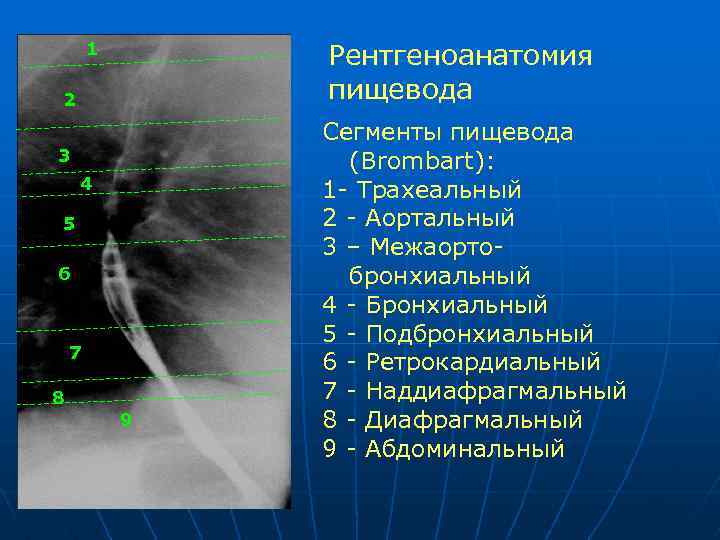

Современные технологии в медицине: рентгенодиагностика заболеваний желудка